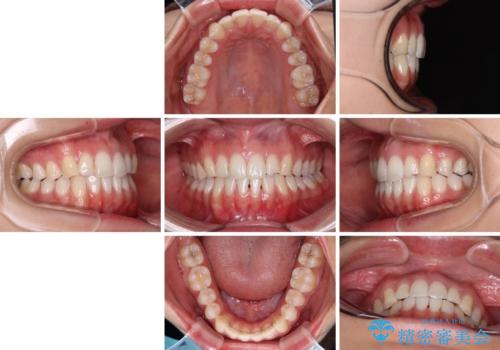

前歯の重なりをインビザライン・モデレートで矯正治療

- 上下前歯の重なりを気にして来院された患者様です。

安価なインビザラインパッケージを用いての治療を希望されており、デコボコの程度が中等度であったため、インビザライン・モデレートを用いて矯正治療を行うこととしました。

インビザライン・モデレートは、製作できるアライナーの枚数に制限があるため、移動可能な量に限りがあるものの、インビザライン・ライトよりも枚数が多いため、幅広い症例に対応可能です。

- 1年2ヶ月

- 治療費の目安: 65万円(税込)費用は治療当時の料金となります